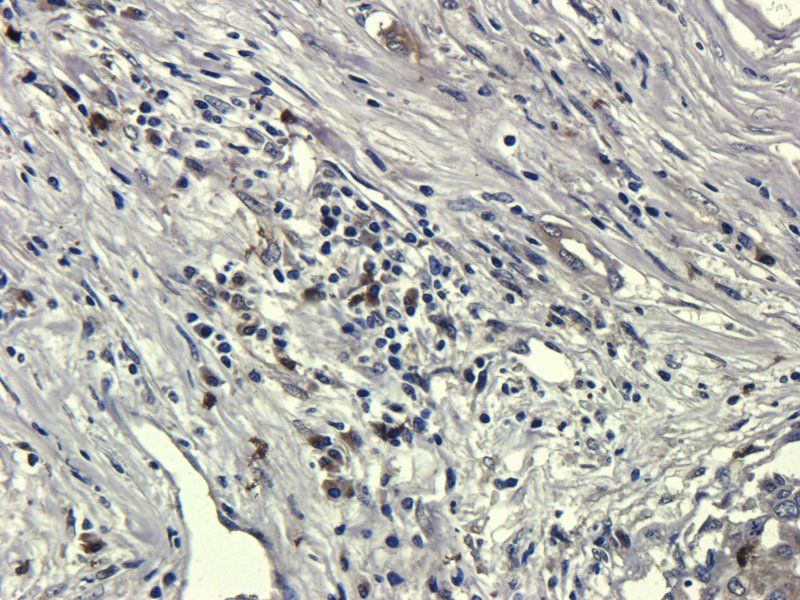

100 μg - OPG antibody [orb247239]Featured

ELISA, ICC, IF, IHC-P, WB

Bovine, Canine, Human, Mouse, Rat

Rabbit

Polyclonal

Unconjugated

100 μg